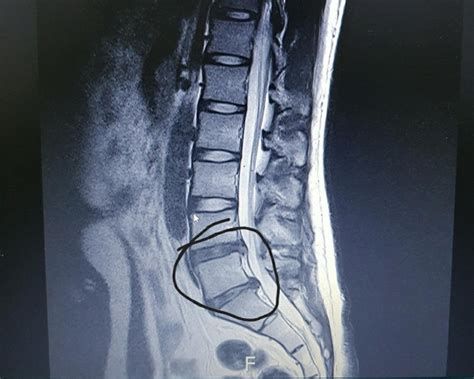

디스크에 과도한 힘이 가해지거나 노화 등으로 인해 섬유륜이 손상되면, 내부의 수핵이 밖으로 튀어나올 수 있습니다. 이때 튀어나온 수핵이 신경을 압박하여 통증이나 감각 이상, 심하면 마비 증상까지 유발할 수 있는데, 이를 흔히 **허리디스크(요추 추간판 탈출증)**라고 부릅니다.